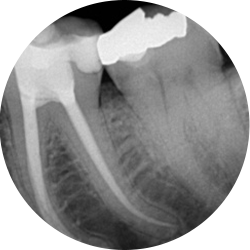

Bacteria associated with decay, deep restorations, fractures, trauma or periodontal disease may irreversibly damage the pulp. In order to preserve a tooth, in which this has occurred, it is necessary to remove the injured, infected tissue. This procedure is known as root canal therapy.

In spite of what you may have heard, modern root canal treatment is similar to having a filling and can be completed in one or two appointments. Following treatment, you’ll feel some tenderness in the tooth or in your jaw. Over-the-counter pain medication will often resolve these temporary symptoms. You can expect a comfortable experience during your appointment.

Your first appointment will generally be a consultation where a throrough examination of your presenting problem will be carried out to diagnose orofacial pain, pulpal injury and to determine if the tooth in question is a good candidate for endodontic therapy.